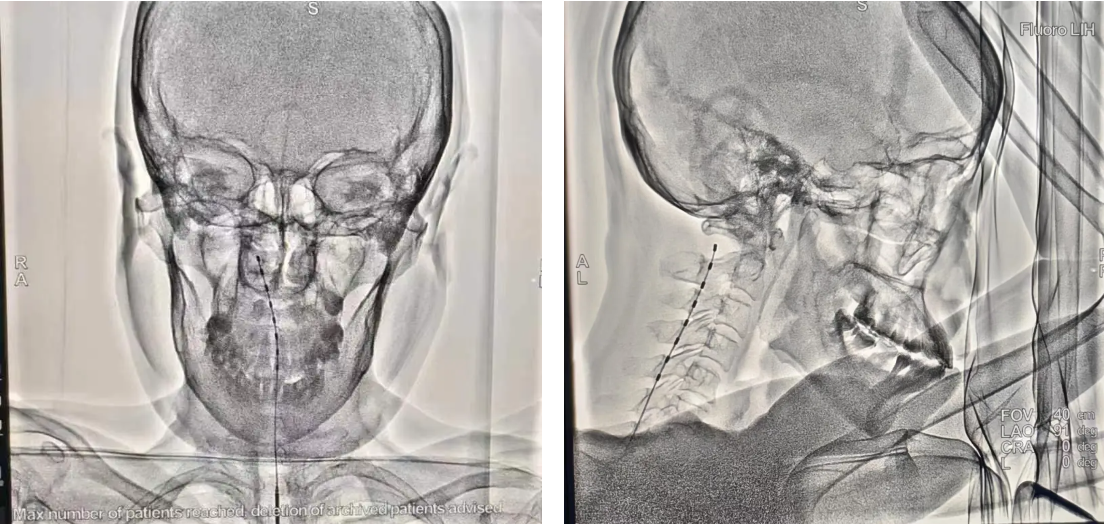

手术台上,疼痛康复医学科的专家们全神贯注、沉着应对,凭借着高超的医术和丰富的临床经验,"披荆斩棘",成功地完成了这一极具挑战性的手术。术后,患者的疼痛状况得到了明显改善。

此次陕北首例脊髓电刺激植入镇痛术的圆满成功,无疑是延大附院疼痛康复医学科在医疗技术领域的一次重大跨越,不仅填补了陕北地区在这一治疗领域的空白,更为广大饱受疼痛折磨的患者带来了崭新的曙光。这一里程碑式的成绩,既得益于医院对医疗科技创新的鼎力支持和高度重视,也离不开疼痛科医疗团队夜以继日地不懈探索与执着追求。